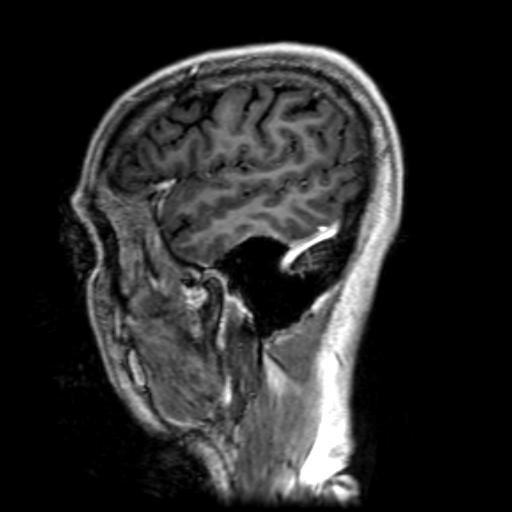

T1-Weighting

This type of MRI study looks at the brain with 25 sagittal (vertical - front to back) cuts.

T1-weighting causes the nerve connections of white matter to appear white, and the congregations of neurons of gray matter to appear gray, while CSF appears dark.

These will show current disease activity if present (which there is none present).